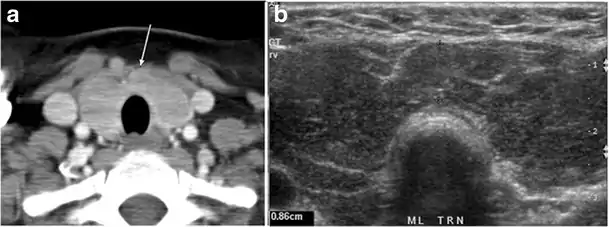

Thyroid nodules that are detected by an imaging study but have not been previously detected or suspected clinically are considered to be ITNs. ITNs are one of the most common incidental findings on neck imaging. ITNs are reported in up to 25% of chest CT scans, and in 16–18 % of cervical region cross-sectional imaging, including CT and MRI scans. The rate of malignancy in the detected ITNs on CT and MRI scans varies from 0% to 11%. Incidentally detected thyroid carcinomas are more likely to be papillary thyroid carcinomas (PTCs) (Fig. 3). Incidentally detected cancers tend to be smaller in size and less likely to have distant metastasis, as compared to clinically suspected thyroid cancers.[1]

Fig. 3. An incidental PTC in a 62-year-old male patient with lymphoma. a, b Enhanced axial CT scan and fused PET/CT scan of the neck demonstrate a well-defined, hypodense right thyroid nodule (white arrow) with high FDG uptake. The FDG-avid uptake in the left side (circle) is related to patient's known lymphoma, which resolved after treatment. c, d Transverse greyscale and sagittal colour Doppler ultrasound of the neck demonstrate a right thyroid irregular hypoechoic lesion with some micro-calcifications (white arrows) and increased vascularity.[1]

On CT scans, a malignant lesion is suspected when the margins are ill-defined and there is extra-thyroid extension, lymph node involvement, or invasion of the surrounding structures. The absence of these features does not exclude malignant tumours, especially papillary, follicular, and medullary thyroid carcinomas (Fig. 3). Therefore, ultrasound is the modality of choice for thyroid lesion evaluation, due to its superior spatial resolution compared to CT examinations. Sonographic features of malignancy are micro-calcifications, acoustic shadowing, anti-parallel orientation, marked hypoechogenicity, irregular or microlobulated margins, and increased vascularity. CT scans lack the ability to detect these reliable sonographic signs of malignancy. Therefore, further management of ITNs, if required, usually begins with thyroid ultrasound and FNA should be considered according to the ultrasound findings.[1]